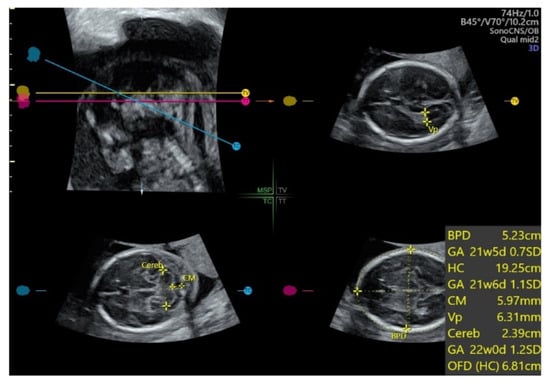

2.1. Fetal Echocardiography and Targeted Neurosonography

5.1. 3D Neurosonography